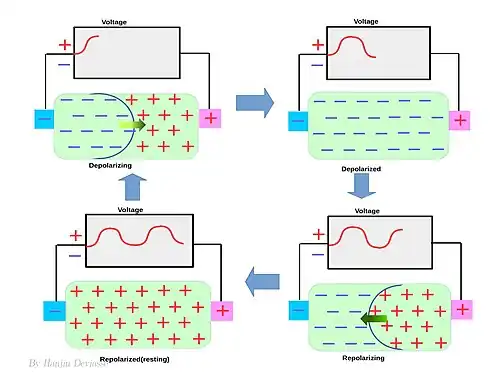

In non-excitable cells, and in excitable cells in their baseline states, the membrane potential has a relatively steady value, called the resting potential. The opening and closing of ion channels can cause a departure from the resting potential. This is called a depolarization if the interior voltage moves to a more positive membrane potential, or a hyperpolarization if the interior voltage becomes more negative . In excitable cells, a sufficiently large depolarization can make an action potential, in which the membrane potential changes rapidly and clearly for a short time (on the order of 1 to 100 milliseconds), often reversing its polarity.

Action potential

In physiology, an action potential is the brief (about one-thousandth of a second) reversal of electric polarization of the membrane of a excited cells such as nerve cell (neuron), muscle cell, endocrine cell and so on.[30]. In neurons, an action potential happens when a neuron sends information down an axon, away from the cell body. In other types of cells, they activate intracellular processes. In muscle cells, for example, an action potential produces the contraction required for all movement. In beta cells of the pancreas, they induce release of insulin.[31] Action potentials in neurons are also known as "nerve impulses" or "spikes", and the temporal sequence of action potentials generated by a neuron is called its "spike train". A neuron that emits an action potential is often said to "fire"[32].

Action potentials are generated by specific voltage-gated ion channels embedded in a cell's plasma membrane.[33] These channels are shut when the membrane potential is near the resting potential of the cell, but stimulation of the cell by neurotransmitters or by sensory receptor cells partially opens channel-shaped protein molecules in the membrane. Sodium diffuses into the cell, shifting that part of the membrane toward a less-negative polarization. If this local potential reaches a critical state called the threshold potential (measuring about −60 mV), sodium channels open completely. Sodium floods inside the cell quickly depolarizes to an action potential of about +55 mV. The declining phase of the action potential is from the closing of sodium channels and the opening of potassium channels, which let a charge about equal to the stage which the cell leaves in the form of potassium ions. Therefore, protein transport molecules pump sodium ions out of the cell and potassium ions in. This restores the original ion concentrations and the membrane is ready for a new action potential.

For instance,in Electrocardiogram(ECG), it is possible to place electrodes on the body surface and measure cardiac potentials as the body behaves as a conductor of the electrical currents by the heart. In the resting, polarized state, no potential difference would exist between the positive and negative electrodes(i.e., isoelectric - flat red line). Within ventricles, when the left side of the tissue becomes depolarized (representing firing of the SA node), a wave of depolarization starts to spread across the ventricles. During this time, some part temporarily remains positive on the outside (polarized) and while some is negative (depolarized); thus, there is a separation of charges which induce a potential difference between the two electrodes. As the wave of depolarization moves toward the positive electrode, conventionally, a positive voltage (upward deflection) is recorded. The voltage reaches its maximal positive value when half the part is depolarized. Once the entire ventricle mass is depolarized (all cells negative on outside), there is no longer be a potential difference and the voltage is the same to the polarized state. When repolarization occurs, starting first with the left side ( SA nodal region) then moving across the ventricle, there will once again be both positive and negative charges on the surface of the ventricle, but this time, the negative charges will be closest to the positive electrode. The wave of repolarization sweeping across the ventricle away from the negative electrode and toward the positive electrode causes, conventionally, a negative voltage (upward deflection in ventricles. It is different according to the part.) to occur. Finally, when all of the cells are repolarized, the measured voltage difference will once again be the same to the initial stage until another wave of depolarization occurs.